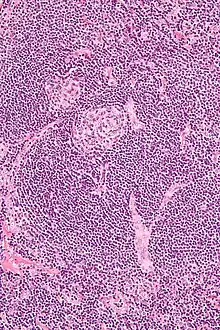

Micrograph of Castleman disease showing hyaline vascular features including atrophic germinal center, expanded mantle zone, and a radially penetrating sclerotic blood vessel ("lollipop" sign). H&E stain. | |

- Hyaline vascular: regressed germinal centers, follicular dendritic cell prominence or dysplasia, hypervascularity in interfollicular regions, sclerotic vessels, prominent mantle zones with an "onion-skin" appearance.[14]